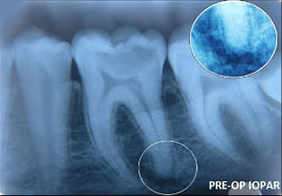

A case of combined REP in one Root and VPT in another Root.

Wound in bone (marked) in one root has healed through REP which is revealed in 6 and 12 months follow up IOPAR, the unaffected pulp in another Root Canal is protected through VPT resulting in the maintenance of validity of Tooth.